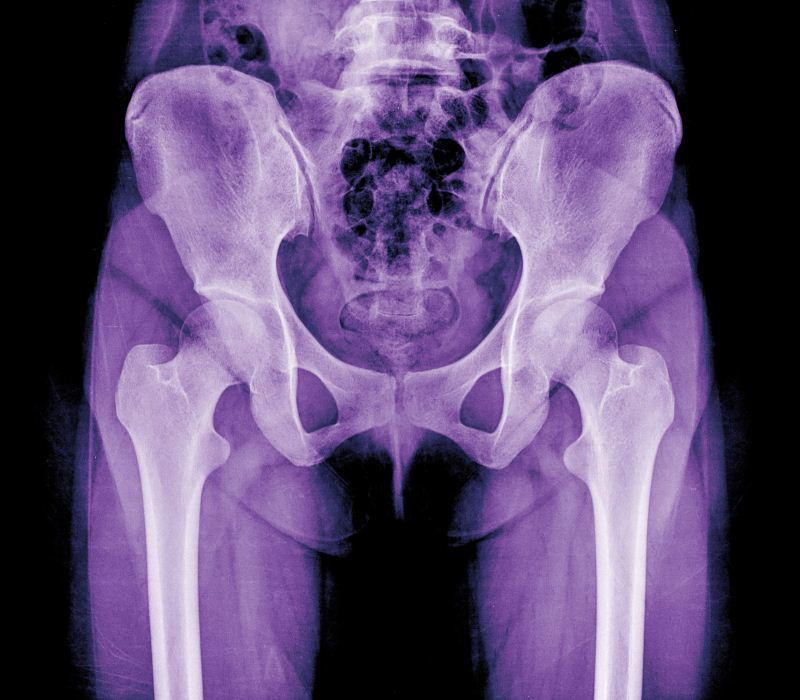

Novedades en la cirugía de prótesis de cadera

Los doctores León González Massieu, jefe de servicio de Cirugía Ortopédica y Traumatología del Hospital Quirónsalud Tenerife, e Ignacio Ríos Bordón, especialista de Cirugía de Cadera del mismo centro, nos detallan la nueva técnica de abordaje, así como sus beneficios